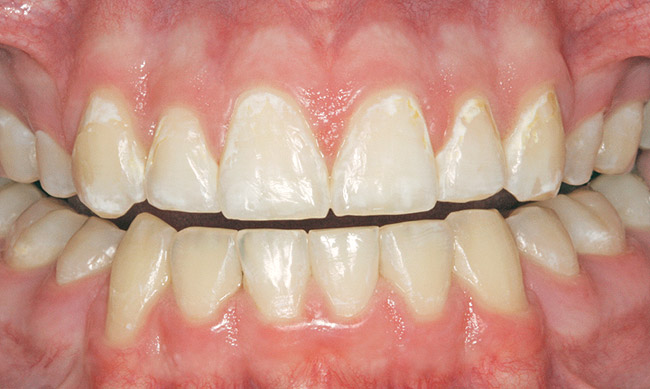

Figure 3  White spot lesions evident after orthodontic therapy (photograph courtesy of S. Paris and H. Meyer-Lueckel).

Figure 3

Figure 4  White spot lesions are imperceptible, blending with natural tooth color, after caries infiltration therapy (photograph courtesy of S. Paris and H. Meyer-Lueckel).

Figure 4